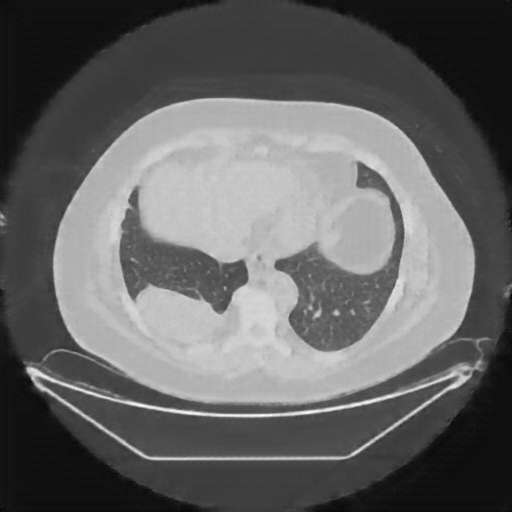

Original NATIVE CT scan (input)

No window - Raw intensity values

Lung window (WL -600, WW 1500 β†’ Low βˆ’1350, High +150)

Mediastinum window (WL 40, WW 400 β†’ Low βˆ’160, High +240)